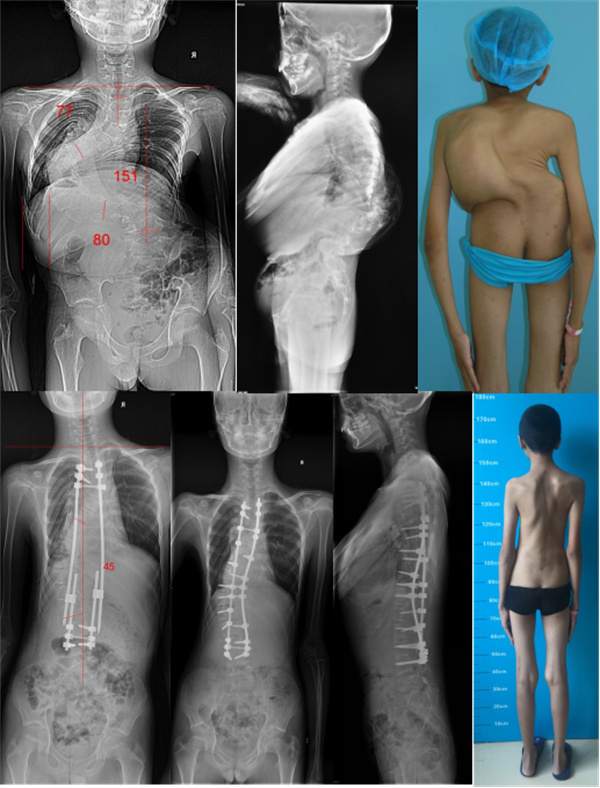

先天性颈胸段畸形

该患者存在严重的颈胸交界区的侧凸及后凸,需高级别截骨术矫正侧凸及后凸,脊髓损伤风险较大。椎弓根发育异常,颈椎椎弓根螺钉置钉困难,椎动脉损伤风险较大。手术时间长,出血多,术后感染等风险较大。